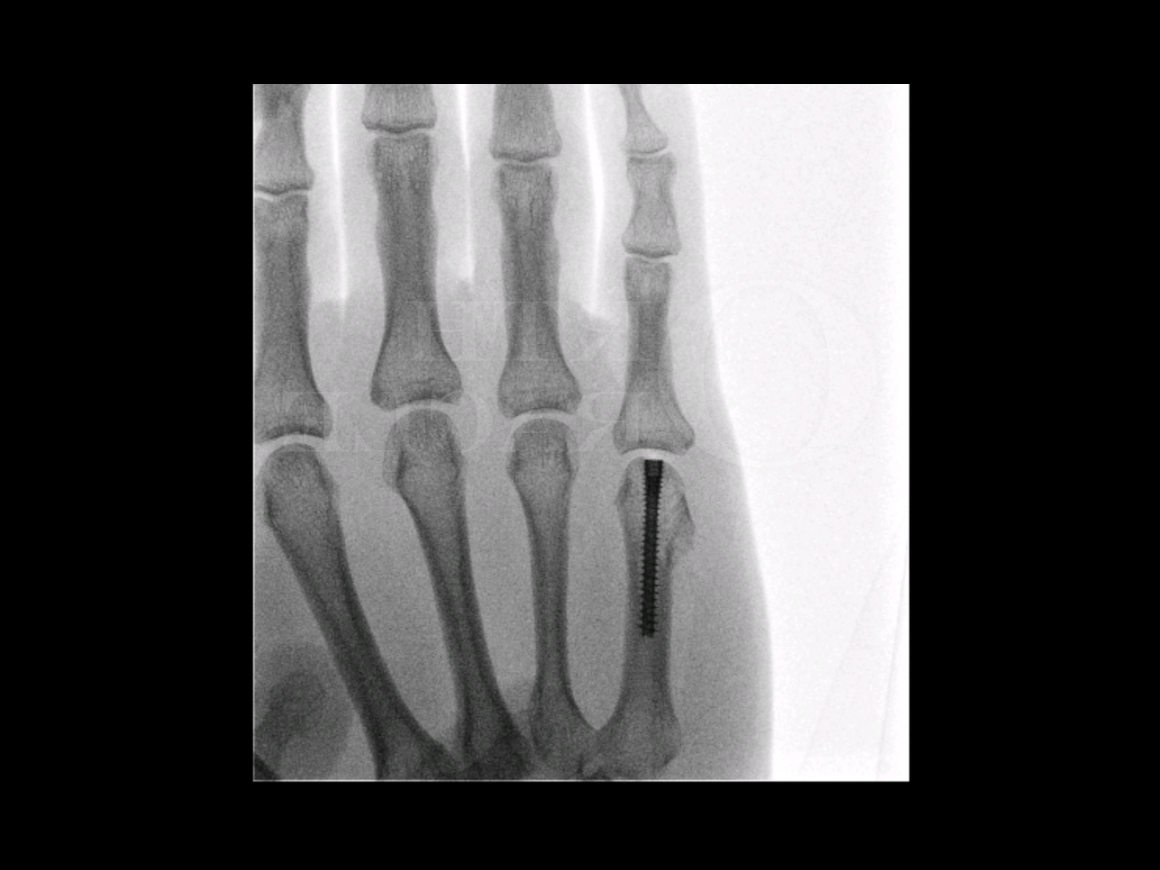

- Stap 3: Operatie: Bij instabiele of complexere breuken kiest men voor een chirurgische ingreep. Indicaties voor operatie zijn bijvoorbeeld: een metacarpaal bot dat in hoekstand staat of verkort is, een boksersfractuur waarbij de fragmenten ver uit elkaar staan, een open breuk. De chirurg kan de botstukken fixeren met metalen pinnetjes (Kirschner-draden) die door de huid steken, of met plaatjes en schroeven op het bot. Soms wordt bij meerdere breuken een combinatie van technieken gebruikt. Na de operatie krijg je meestal een gips of spalk voor een tweetal weken ter bescherming. Hierna begint geleidelijke mobilisatie onder begeleiding van een handtherapeut.

Een boksersfractuur is een veelvoorkomende breuk van een middenhandsbeentje in de hand, meestal door een klap of ongeval. Het is een type metacarpaal fractuur dat zich kenmerkt door een ingezakte knokkel en pijn in de hand. De diagnose wordt gesteld met een röntgenfoto en de behandeling bestaat vaak uit gipsimmobilisatie voor ongeveer een maand. In ingewikkelde gevallen of bij verkeerde stand biedt een operatie met pinnen of plaatjes een goede oplossing, zodat het bot correct geneest. Met de juiste opvolging, inclusief handtherapie na immobilisatie, is de prognose uitstekend: het gebroken middenhandsbeentje groeit doorgaans goed weer aan elkaar en de handfunctie herstelt grotendeels.